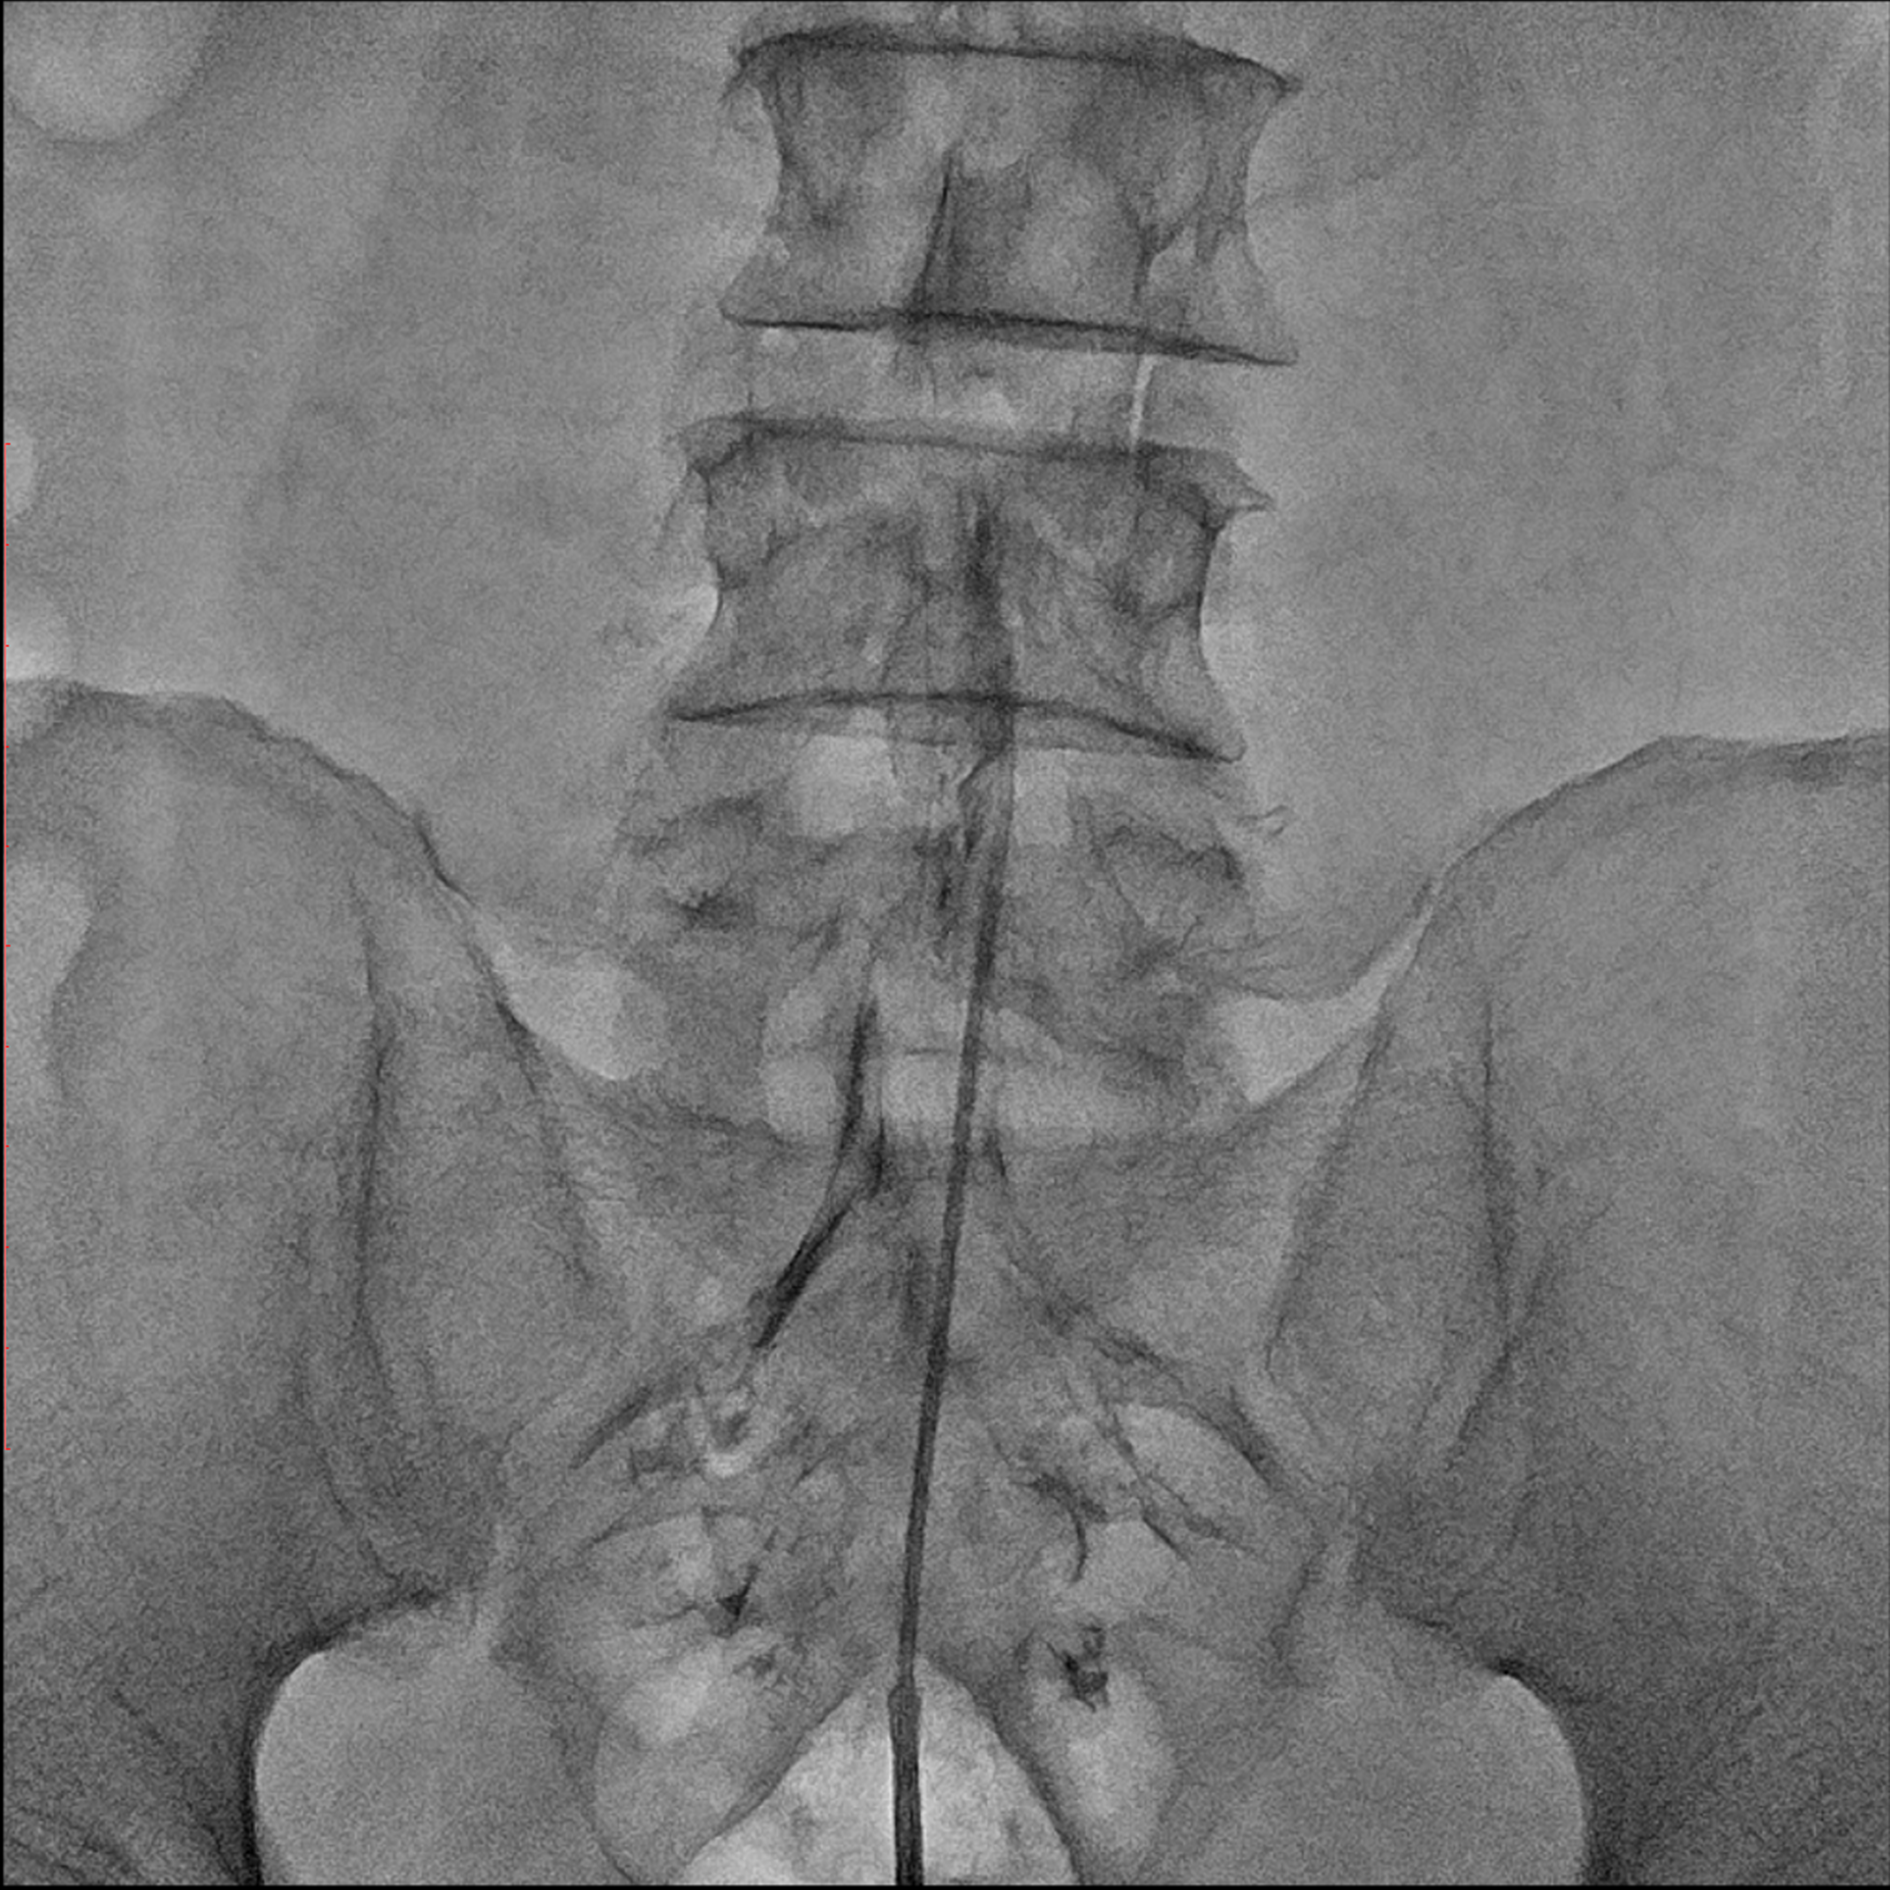

Editorial/Editor's Pick 경막외 유착박리술, Epidural Neuroplasty by Pharmacopuncture Research Lab 2026. 1. 3. 공유하기 게시글 관리 Acupuncture Radiology 관련글 MRI 요양급여의 적용기준 및 방법에 관한 세부사항 MRI 요양급여의 적용기준 및 방법에 관한 세부사항 [신구대조표] Association of AI‑determinedKellgren–Lawrence grade Portable X-ray